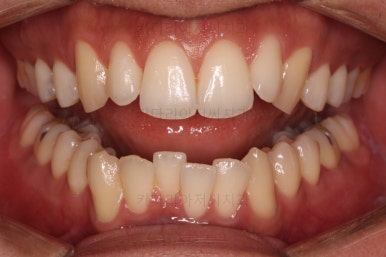

한참을 셋팅한 방향으로 치열을 당겨줍니다.

중간평가를 자주 하게 됩니다.

입을 다물었을 때 턱끝이 점점 자연스러워지는 느낌이네요. 윗입술 부위가 둥글게 돌출되어 보이던 느낌도 점점 좋아지고 있고요.

아직은 환자분이 개선을 더 원하기 때문에 현재의 방식으로 더 진행하기로 했습니다.

계속 진행합니다.

또 다시 얼굴모습을 평가하고 환자분과 개선할 점에 대해 의견을 나눕니다.

옆모습은 상당히 만족하고 계셨고, 웃을 때의 치열의 중앙선을 좀 더 맞추고 싶어하셨습니다.

여러 가지를 더 원하시는 만큼 개선한 뒤 부산연제구교정 치료를 마무리하기로 했습니다.